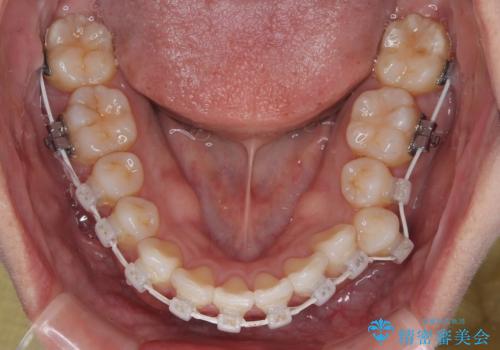

初診時、上下顎ともに歯列の不正が認められ、特に左下の小臼歯が大きく歯列から外れている状態でした。その影響により、下顎の正中が左側へシフトしており、見た目だけでなく噛み合わせにも影響が出ていました。

左下の小臼歯をきれいに歯列内へ並べるためには、まず十分なスペースの確保が必要でした。

そこで本症例では、上顎右側にアンカースクリュー(矯正用インプラント)を埋入し、そこからゴムかけ(顎間ゴム)を行うことで、下顎の正中を右方向へコントロール。

これにより、左下小臼歯がく並ぶためのスペースを確保することができました。

矯正中の見た目にも配慮し、プラスチックブラケット+コーティングワイヤーの目立ちにくい審美装置を採用しました。